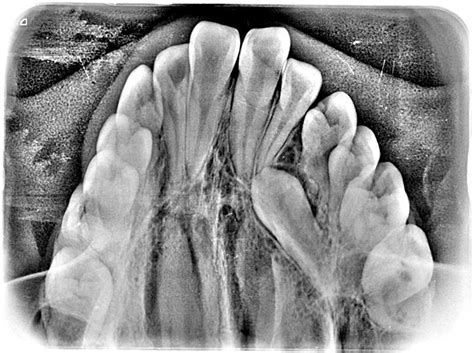

Registros Radiográficos Pretatamiento y Cefalometría

La ortopantomografía inicial (fig. 4) muestra una dentición mixta, iniciando el segundo período de recambio, con obturaciones a nivel de 16 y 26 y cóndilos mandibulares simétricos.

Figura 4. Ortopantomografía pretratamiento.